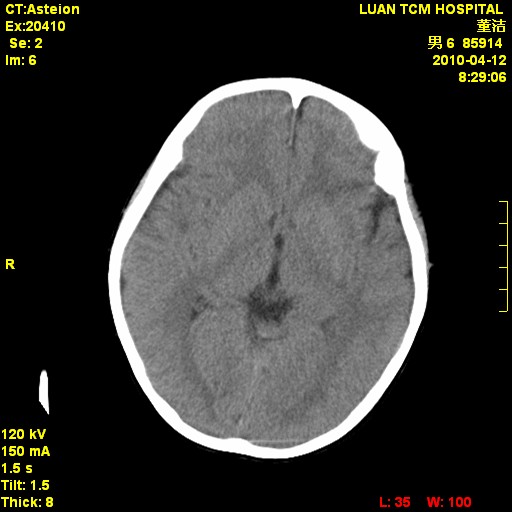

标题: PED3404:有结果,先猜猜这是啥病表现?男,12岁。 [打印本页]

标题: PED3404:有结果,先猜猜这是啥病表现?男,12岁。

无病史无骨窗,无水肿无占位征象,先猜颅骨血管瘤或者嗜酸性肉芽肿

无病史无骨窗,12岁可以可考虑白血病等。

鉴别:骨肉瘤、ewing's瘤、骨淋巴瘤、板障型脑膜瘤、嗜酸性肉芽肿等

右侧额顶部自颅板向内近似半圆高密度影,周围无明显水肿,考虑:脑外血肿?脑膜瘤?淋巴瘤?